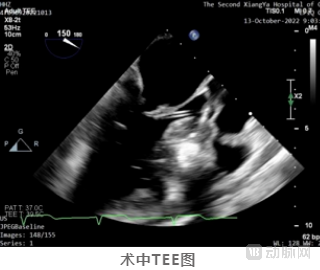

术中,方臻飞教授熟练操控DragonFire,根据术前确定的消融策略,连续对前间隔、中间隔基底部最为肥厚的心肌区域进行了精准的定位、穿刺,并进行对应能量范围的消融。

术后彩超提示SAM征消失,二尖瓣反流改善,LVOT收缩期流速由术前6.1m/s降低至术后2.1m/s,左室流出道峰值压差更是从术前的150mmHg下降至17mmHg,术中即刻消融效果使得流出道压差减小量高达133mmHg。

患者术后即拔管,临床症状明显改善,无任何例如心律失常、左心低排等oHCM术后常见并发症。患者于术后一周顺利出院。